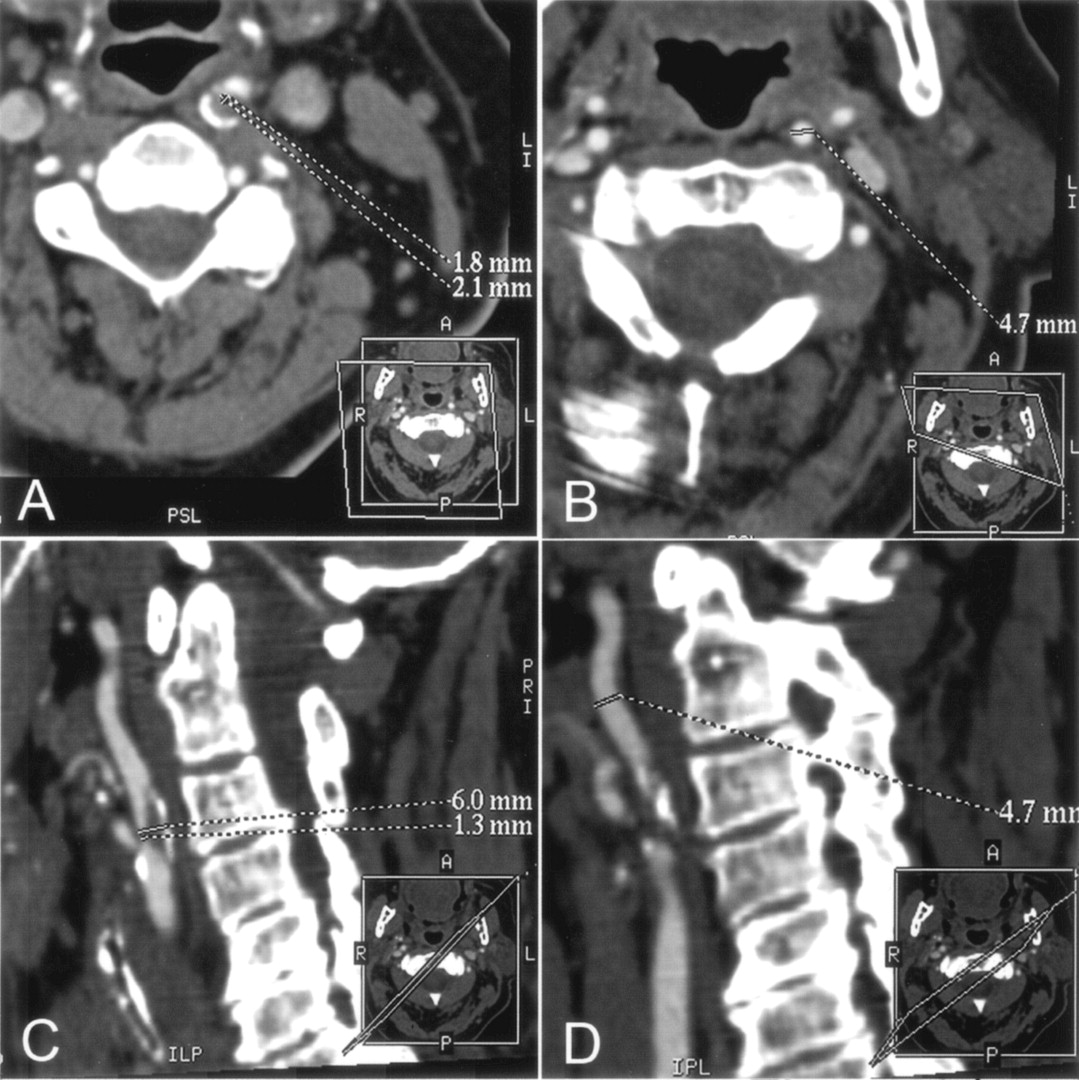

A–D, CT angiographic MPR images of the left ICA at the stenosis level (A and C) and at the distal extracranial ICA as the chosen reference level (B and D) for assessment of stenosis degree with NASCET criteria. Dotted lines indicate sites of measurement of vessel diameter. Every view was tilted according to the patient’s individual anatomy; the tilted planes are shown in small boxes in the right lower corner of each image.

A and B, Cross-sectional MPR images (data were reformatted with the double oblique mode) illustrate the accurate cross-section of the artery at the stenosis level (A) and at the chosen reference level (B). At the stenosis level, the minimum diameter was determined with an additional measurement perpendicular to the smallest diameter.

C and D, Oblique sagittal MPR images tilted along the course of the obliquely oriented ICA at the level of stenosis (C) and at the chosen reference level in the distal extracranial ICA (D) . At the stenosis level, the actual diameter of the entire ICA (upper dotted line in C), including the patent vessel lumen and the plaque, is shown.